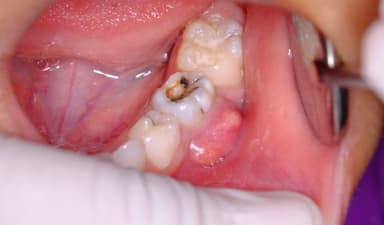

– Lỗ sâu trên bề mặt răng: Có thể nhìn thấy bằng mắt thường hoặc cảm nhận bằng lưỡi – răng có lỗ nhỏ, sậm màu hoặc thô ráp bất thường.

Khi vi khuẩn sâu răng tấn công lớp ngà và men răng mà không được điều trị kịp thời, chúng sẽ tiếp tục xâm nhập sâu vào tủy – nơi tập trung nhiều dây thần kinh và mạch máu quan trọng. Hậu quả là người bệnh có thể bị viêm tủy răng, gây ra những cơn đau nhức dữ dội, đặc biệt vào ban đêm hoặc khi ăn uống đồ nóng, lạnh. Một số dấu hiệu nhận biết viêm tủy do đau sâu răng bao gồm: đau răng kéo dài và dữ dội, răng trở nên nhạy cảm hơn với nhiệt độ, vùng nướu quanh răng có thể sưng nhẹ, thậm chí xuất hiện triệu chứng sốt nhẹ. Viêm tủy nếu không được chữa trị đúng lúc có thể dẫn đến hoại tử tủy và lây lan sang các mô lân cận, làm tổn hại nghiêm trọng đến sức khỏe răng miệng.

5.2. Áp xe răng

Áp xe răng là tình trạng nhiễm trùng có mủ hình thành ở chân răng hoặc vùng mô nướu xung quanh, được xem là một trong những biến chứng nguy hiểm do đau sâu răng không được điều trị triệt để. Khi áp xe phát triển, người bệnh thường gặp các triệu chứng như: đau nhói kéo dài, cơn đau có thể lan đến tai, hàm hoặc cổ; hơi thở có mùi hôi, kèm theo vị đắng trong miệng; sưng nướu hoặc mặt, thậm chí có thể xuất hiện mủ; sốt cao và cảm giác mệt mỏi toàn thân. Nếu không được can thiệp kịp thời, ổ áp xe có nguy cơ vỡ ra, khiến vi khuẩn lan rộng sang các cơ quan khác, gây nhiễm trùng toàn thân và có thể đe dọa đến tính mạng.